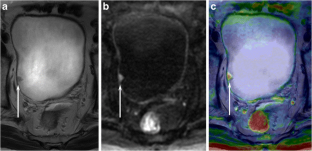

Fig. 1